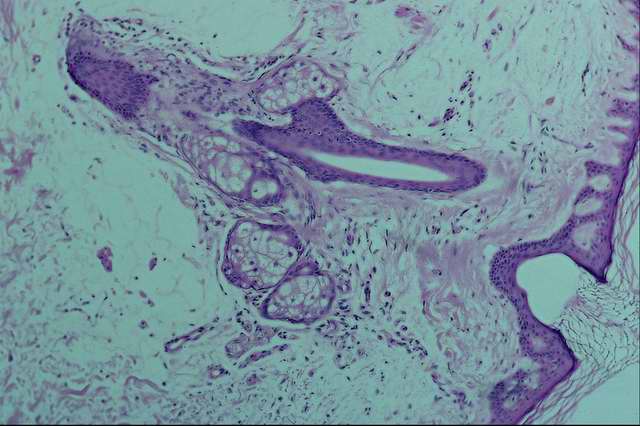

Причины: нарушение обмена веществ в организме — белковая, минеральная (недостаток цинка, кальция, фосфора) или витаминная недостаточность (гиповитаминоз А, особенно у птиц, крупного рогатого скота и свиней, пеллагра и др.); инфекционные болезни, связанные с воспалением кожи (дерматофитозы, чесотка, парша и др.); физические и химические раздражающие воздействия на слизистые оболочки и кожу; хроническое воспаление слизистых оболочек; иногда наследственные заболевания (ихтиоз — образование роговых наслоений на коже, напоминающих рыбью чешую или панцирь черепахи). Избыточное образование рога наблюдают в бородавках, канкроиде (ракоподобной опухоли) и дермоидных кистах.

Патогенез роговой дистрофии связан с избыточным или нарушенным синтезом керотина в эпидермисе кожи и в ороговевшем эпителии слизистых оболочек. Образование рогового вещества в слизистых оболочках пищеварительного тракта, верхних дыхательных путей и половых органов сопровождается заменой железистого эпителия ороговевающим плоским многослойным.

Гистологически при паракератозе выявляют утолщение эпидермиса в результате гиперплазии клеток мальпигиевого слоя и избыточного накопления рогового вещества. В слизистых оболочках кожного типа и в эпидермисе кожи возможно сосочковое утолщение эпидермиса из-за гиперплазии слоя шиловидных клеток и удлинения шиловидных отростков. Такие поражения называют акантозом (от греч. akantha— шип, игла).

При пара- и гипокератозе выражена атрофия зернистого слоя, роговой слой рыхлый, с дискомплексированными клетками, имеющими палочковидные ядра (неполное ороговение).

Макроскопически в местах патологического ороговения (распространенного или местного) кожа утолщена, с избыточным разрастанием рогового слоя. Она утрачивает эластичность, становится шероховатой и жесткой, образуются сухие утолщения и мозоли. При паракератозе роговой слой утолщен, рыхлый, с повышенным слущиванием роговых чешуек, иногда выпадением волос. У взрослых животных, особенно у молочных коров, отмечают неправильный рост копытного рога, который утрачивает глазурь и растрескивается.

При лейкоплакии (от греч. leukos — белый, plax, axos — плита) на слизистых оболочках образуются различного размера очаги ороговевшего эпителия в виде возвышающихся тяжей и бляшек серо-беловатого цвета.